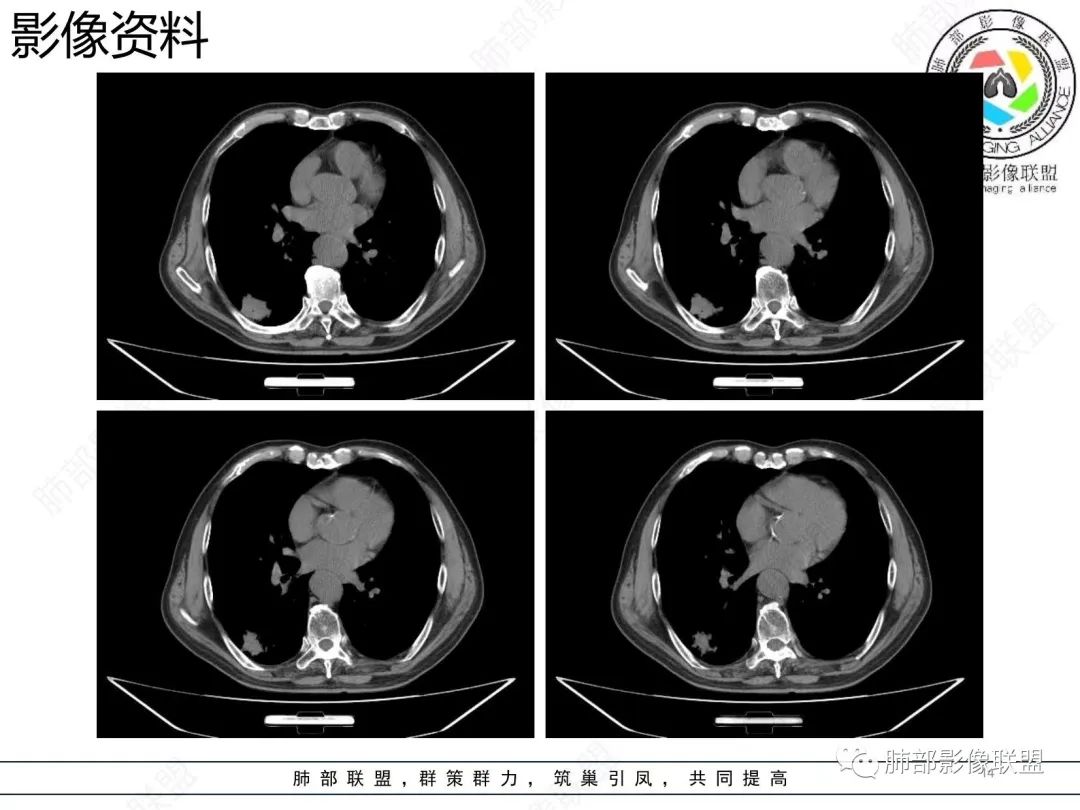

老年男性,右肺下叶混合磨玻璃密度结节,可见血管弯征,首先考虑肺腺癌。

右肺下叶背段不规则结节,边界欠清,可见少许晕征,另见胸膜凹陷征及血管弯,考虑腺癌,鉴别隐球菌。

右肺下早不规则结节,周围少许磨玻璃晕,胸膜有牵拉凹陷,虽然部分边界平直,但血管受牵拉弯曲,首先还是考虑肿瘤,腺癌

右肺下叶背段斑片影,边缘平直、局部膨隆,可见磨玻璃密度影,界清,胸膜牵拉,良恶性需要进一步鉴别,倾向隐球,鉴别粘液腺癌。

老年男性,右肺下叶胸膜下结节,边缘见清晰磨玻璃密度影及少许索条,支气管进入后截断,周围血管弯,考虑腺癌,鉴别隐球菌

右肺下叶胸膜下混合密度结节,分叶、毛刺,磨玻璃边界尚清晰,血管集束,支气管进入阻断,考虑腺癌

右肺下叶背段胸膜下肿块,边缘不规则,分叶,毛刺,有磨玻璃,边界清,近肺门侧见血管聚集,支气管进入后闭塞,右肺下叶肺静脉牵拉扭曲。诊断,支持腺癌

结节型粘液腺癌,具有血管弯,支气管截断,磨玻璃边界清楚等恶性征象,同时磨玻璃内部较糊,似清非清,不符合普通腺癌附壁生长特点,更像局限的粘液成分。收缩力不强,胸膜局部微积液,内部小空洞(考虑局部粘液排除形成),所以考虑结节型粘液腺癌。

区别1:结节期(影像说结节型)粘液腺癌,粘液成分还大多数局限于粘液腺癌细胞的胞浆中,没有飘出去,所以粘液密度不明显,周围的磨玻璃成分大多数还是分散于肺泡壁上的粘液腺癌细胞,所以边界相对较清楚(时间越晚,飘出去的粘液越多,边界就会越不清楚了),因为胞浆中的粘液成分显得较糊,有点似清非清。而普通腺癌附壁生长的腺癌细胞胞浆中没有粘液,所以非常清楚。

区别2:粘液腺癌的MGGN收缩力不强,普通腺癌的MGGN收缩力明显。